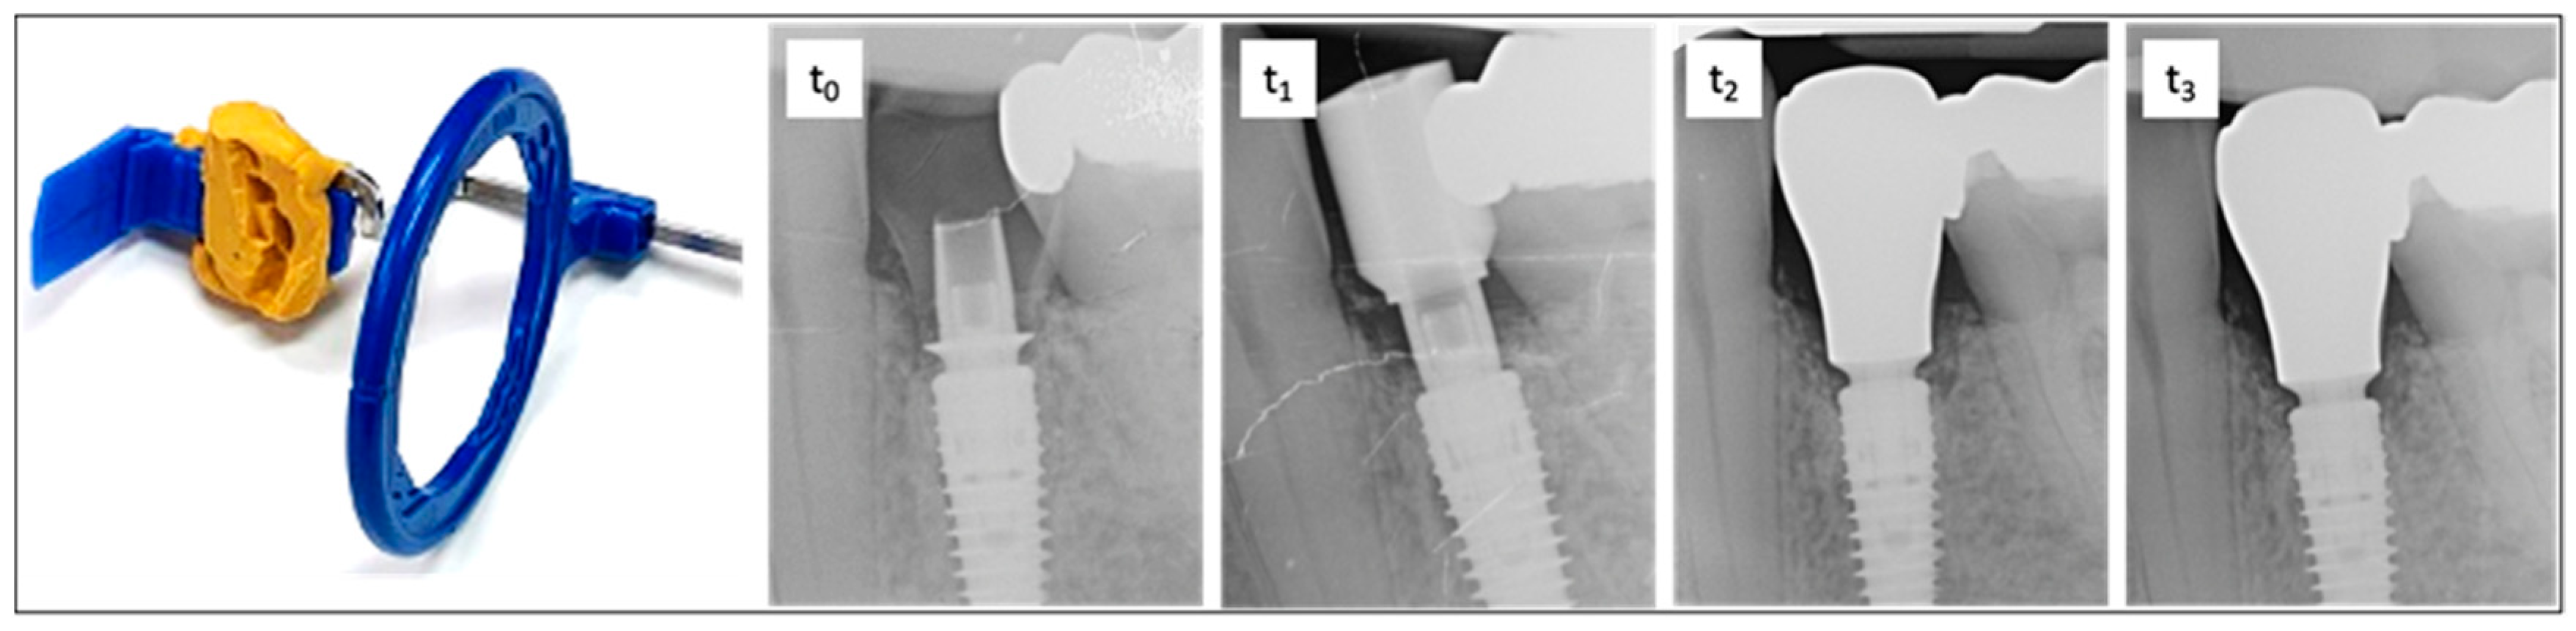

To assess the vertical bone changes, intraoral radiographs were taken at the following time points: implantation (t0), six months postoperatively or at the placement of the final crown (t1), one-year follow-up (t2), and two-year follow-up (t3). These radiographs were obtained using the right-angle technique with digital storage phosphor plates (VistaScan Image Plate Plus and VistaScan Perio, Dürr Dental, Bietigheim-Bissingen, Germany; ProX, Planmeca©, Helsinki, Finland). A Rinn film holder was used, which was individualized for each patient with an impression silicone (Panasil® Putty, Kettenbach©, Eschenburg, Germany) to ensure the comparability of the radiographs in terms of position, angle, and the distances to be measured (Figure 3).

Figure 3. On the left is the radiographic film holder, which was customized with malleable silicone to ensure a reproducible position for all imaging sessions. On the right is an exemplary sequence of dental radiographs taken at time points t0, t1, t2, and t3. t0—time of implantation. The subcrestal position of the implant and bonding base is clearly visible. Adaptation using the Bone Profiler System enabled the insertion of the provisional restoration by removing obstructive proximal bony overhangs and shaping the emergence profile. t1—six months after implant placement with a scan body. t2—one-year follow-up showing bone remodeling and the final restoration. t3—two-year follow-up demonstrating stable bone conditions around the implant and completed remodeling.